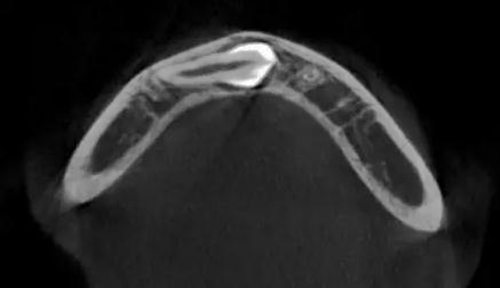

CBCT顯示